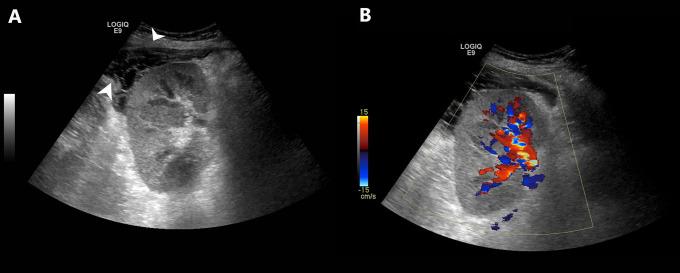

Educational Case: Kidney Transplant Rejection.